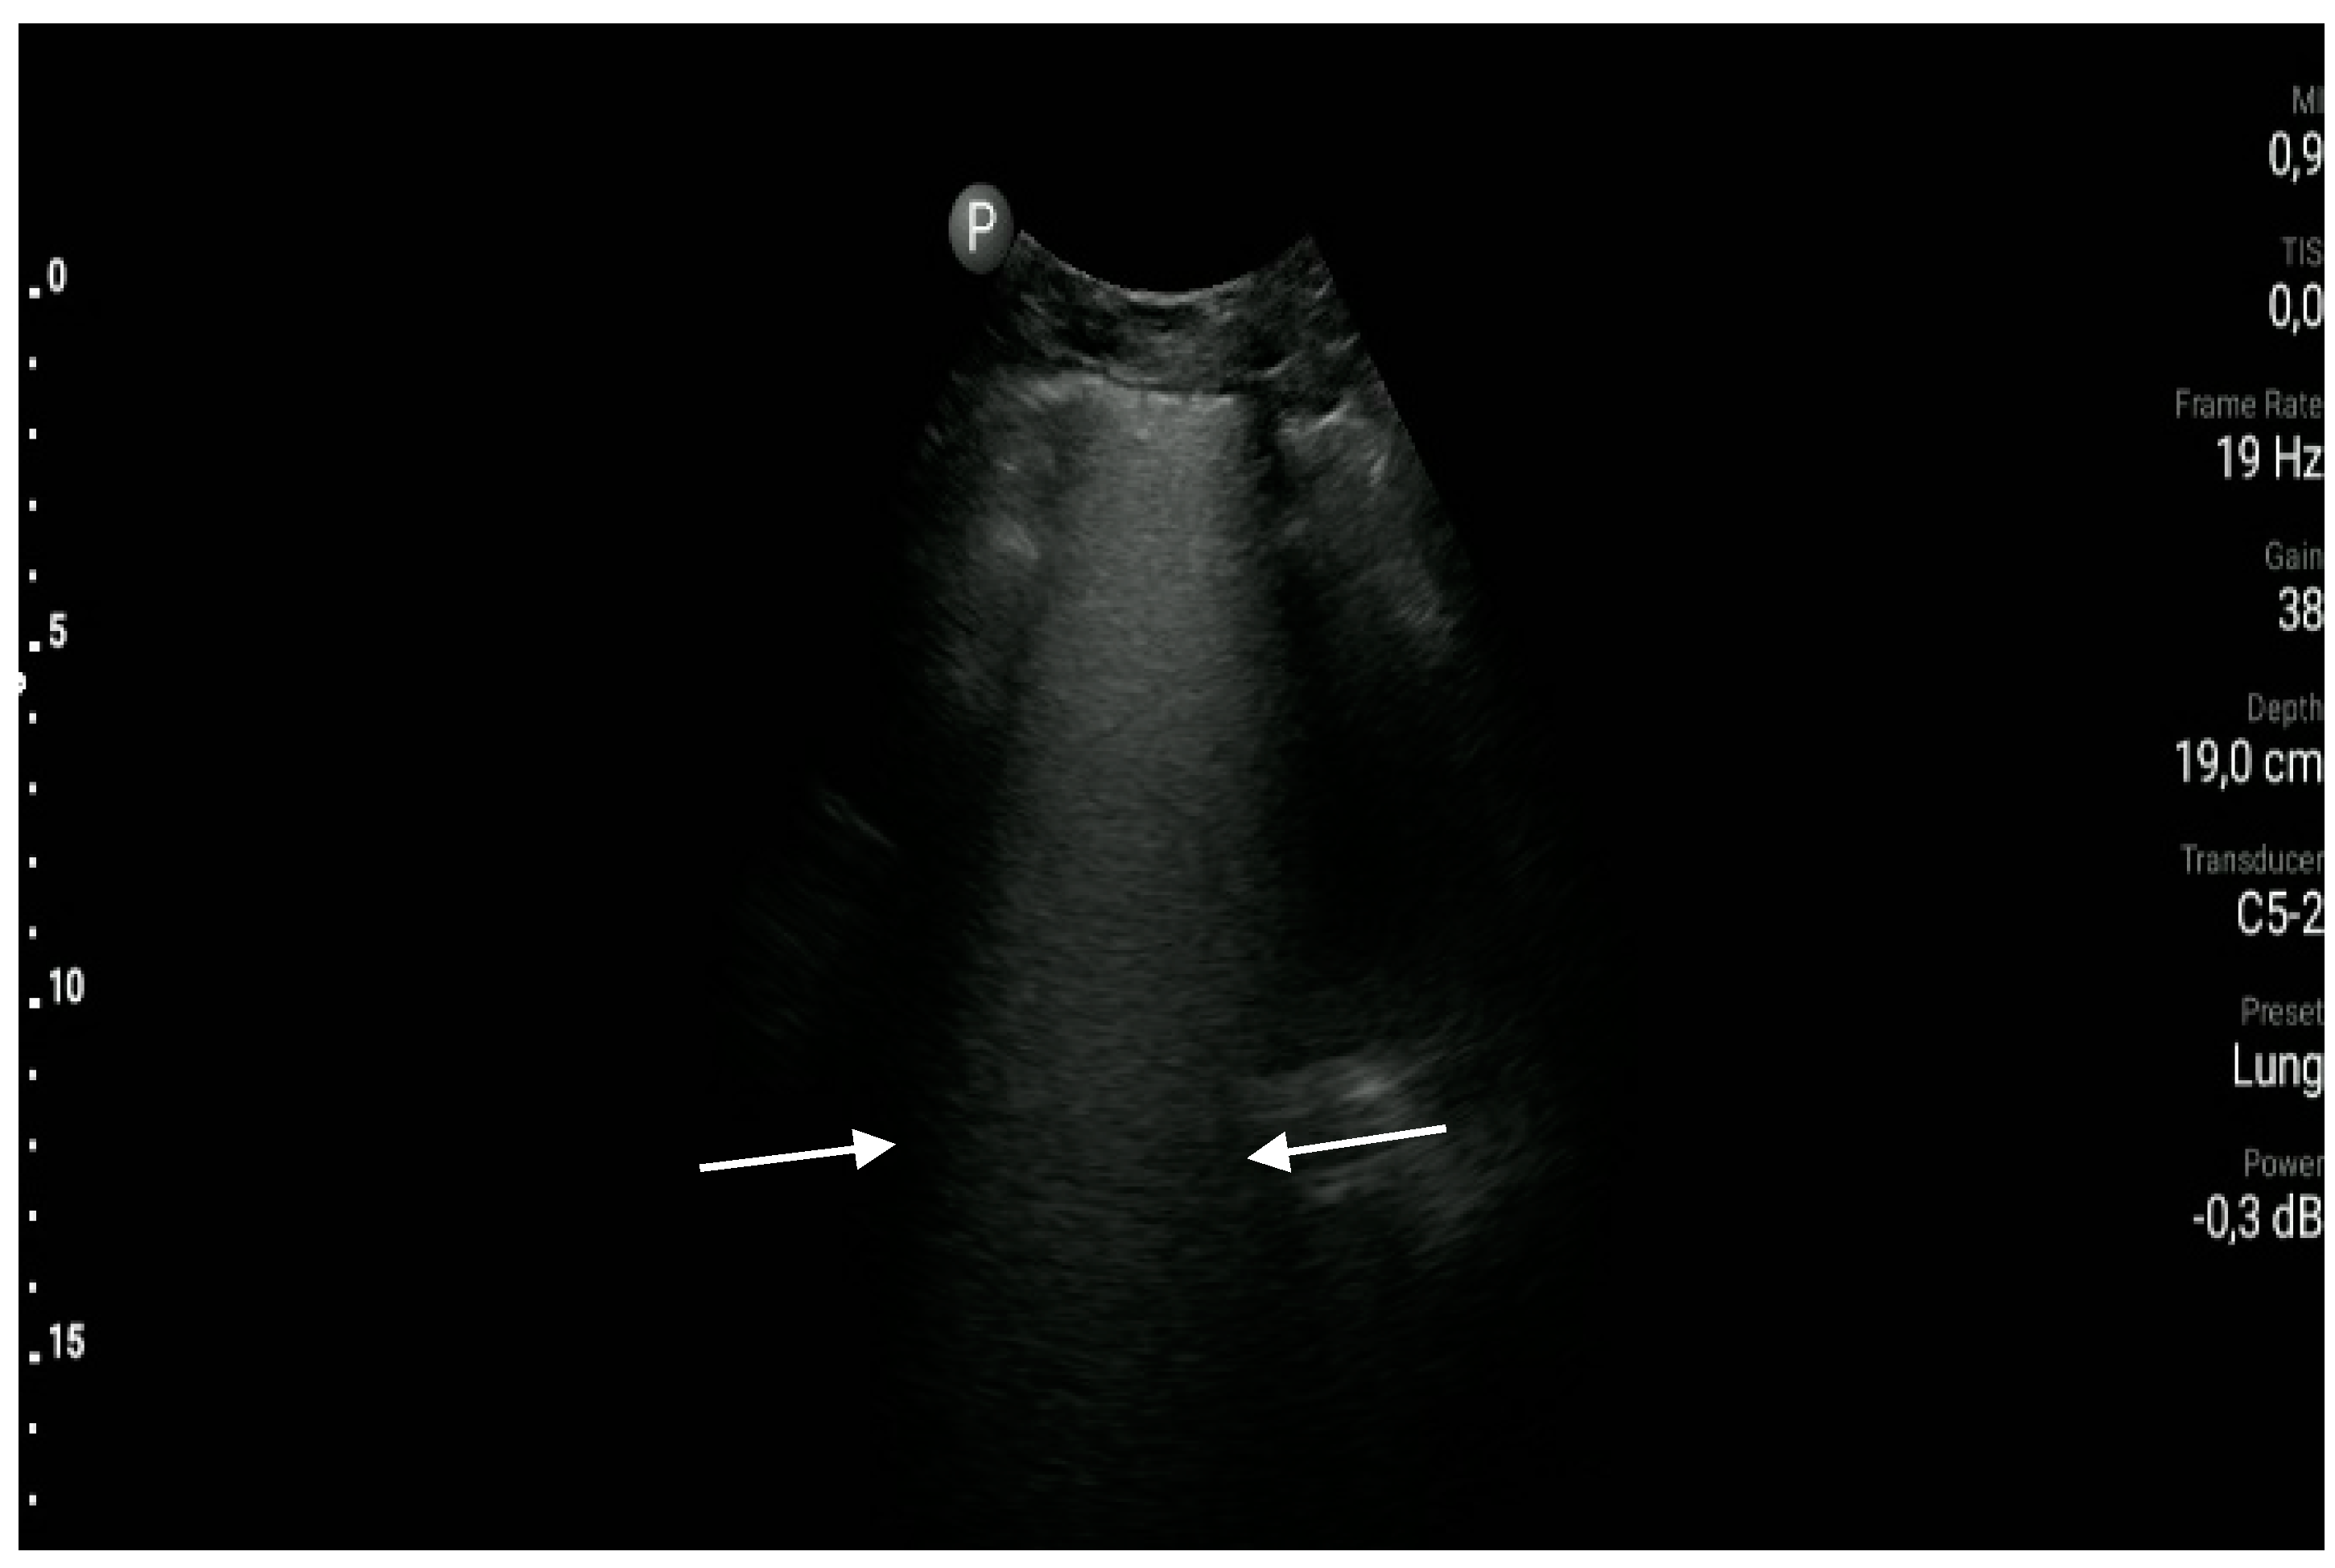

3.1.2. Pleural Effusion

- Chest ultrasound is a more sensitive and more specific diagnostic imaging technique for pleural effusion than chest X-ray. (A1)

- Sonomorphology of pleural fluid in combination with clinical data may suggest its type. (C1)

- Parietal pleural thickening (more than 2 mm) and/or detection of focal lesions within the parietal pleura may suggest a metastatic fluid type.